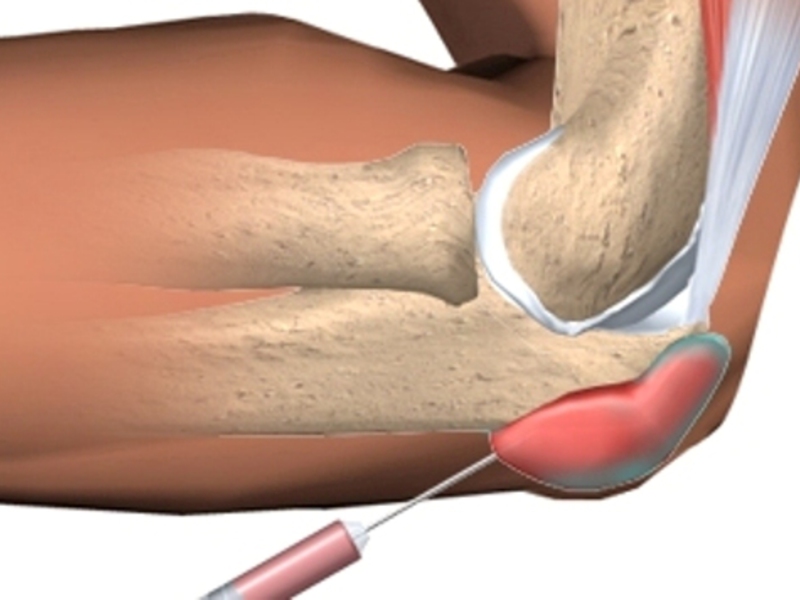

Медицинские состояния: Септический артрит коленного сустава